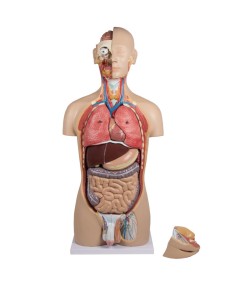

Scopri il Mondo dell’Anatomia con Modelli anatomici di Precisione

Modelli Anatomici Dettagliati per Ogni Necessità

Dal cranio in 22 parti con incastri magnetici ai modelli di colonna vertebrale, da quelli di articolazioni a quelli di cuore, ogni pezzo della nostra collezione è progettato per un’immersione totale nello studio dell’anatomia umana. I nostri modelli, realizzati tramite scansioni di ossa vere, garantiscono un’esperienza tattile autentica e una fedeltà di peso quasi identica agli originali.

Strumenti Didattici Innovativi per l’Educazione e la Pratica Medica

Essenziali per studenti e professionisti, i nostri modelli anatomici sono strumenti didattici che permettono di osservare le strutture anatomiche con precisione, eliminando la necessità di dissezioni o studi invasivi. Sono inoltre utili per spiegare ai pazienti le patologie, rendendo la comunicazione più efficace e risparmiando tempo prezioso.